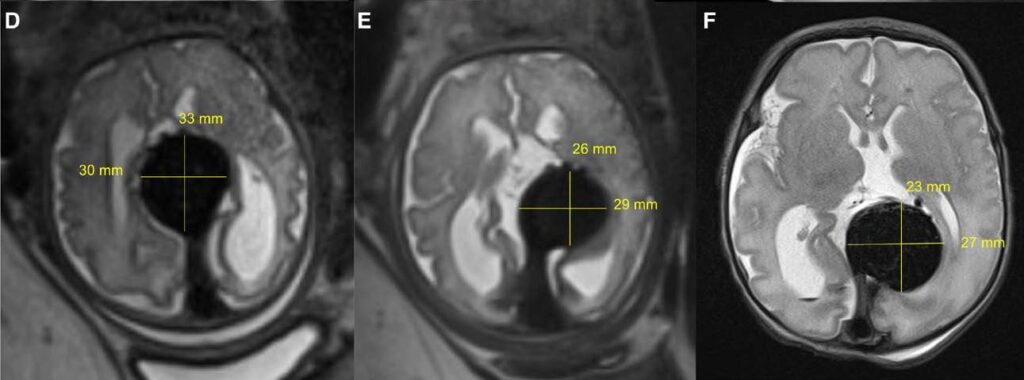

Снимки на мозъка на бебето, показващи размера на аномалията в хода на нейното свиване. От ляво надясно: преди емболизация, непосредствено след нея и непосредствено след раждането на бебето. (Orbach et al., Stroke, 2023)

Затова Орбах и колегите му предприемат клинично проучване, за да проверят възможността за лечение на състоянието преди раждането. Техният пациент е плод на 34 седмици и 2 дни (пълният термин е около 40-та седмица) и те използват ултразвук, за да се ориентират при извършване на процедурата по емболизация.